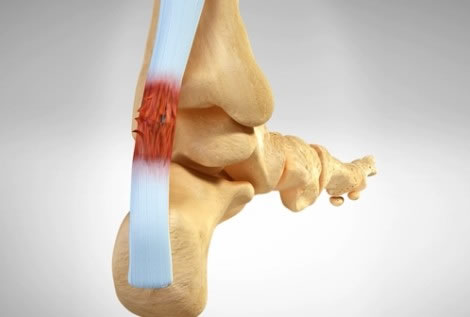

El tobillo es la articulación que conecta la pierna con el pie. En ella se relacionan tres huesos: tibia, peroné y astrágalo. Esta estructura ósea está fuertemente reforzada por músculos, tendones y potentes ligamentos que la estabilizan.